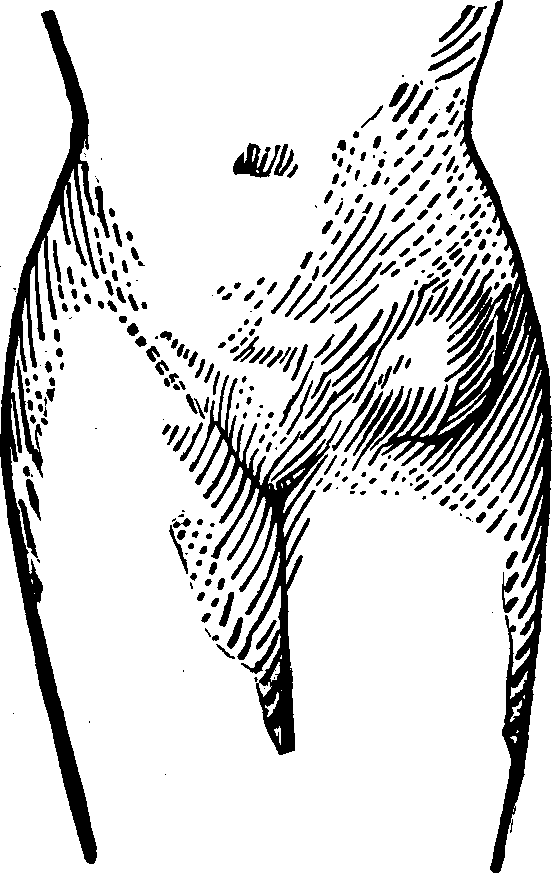

Flexions and Versions of the Womb. Flexion of the uterus, in which it is bent upon itself, as illustrated in Fig. 10, produces a bending of the cervical canal, constricting or obliterating it, and thus preventing the passage of spermatozoa through it. Version of the uterus [pg 710]in which its top, or fundus, falls either forward against the bladder (anteversion), as illustrated in Fig. 11, or backward against the rectum (retroversion), may close the mouth of the uterus by firmly pressing it against the wall of the vaginal canal, and thus prevent the passage of spermatozoa into the womb. 'The treatment of these several displacements will be considered hereafter. We may here remark, however, that they can be remedied by proper treatment. Our mechanical movements, manipulations, and kneadings are invaluable aids in correcting these displacements.